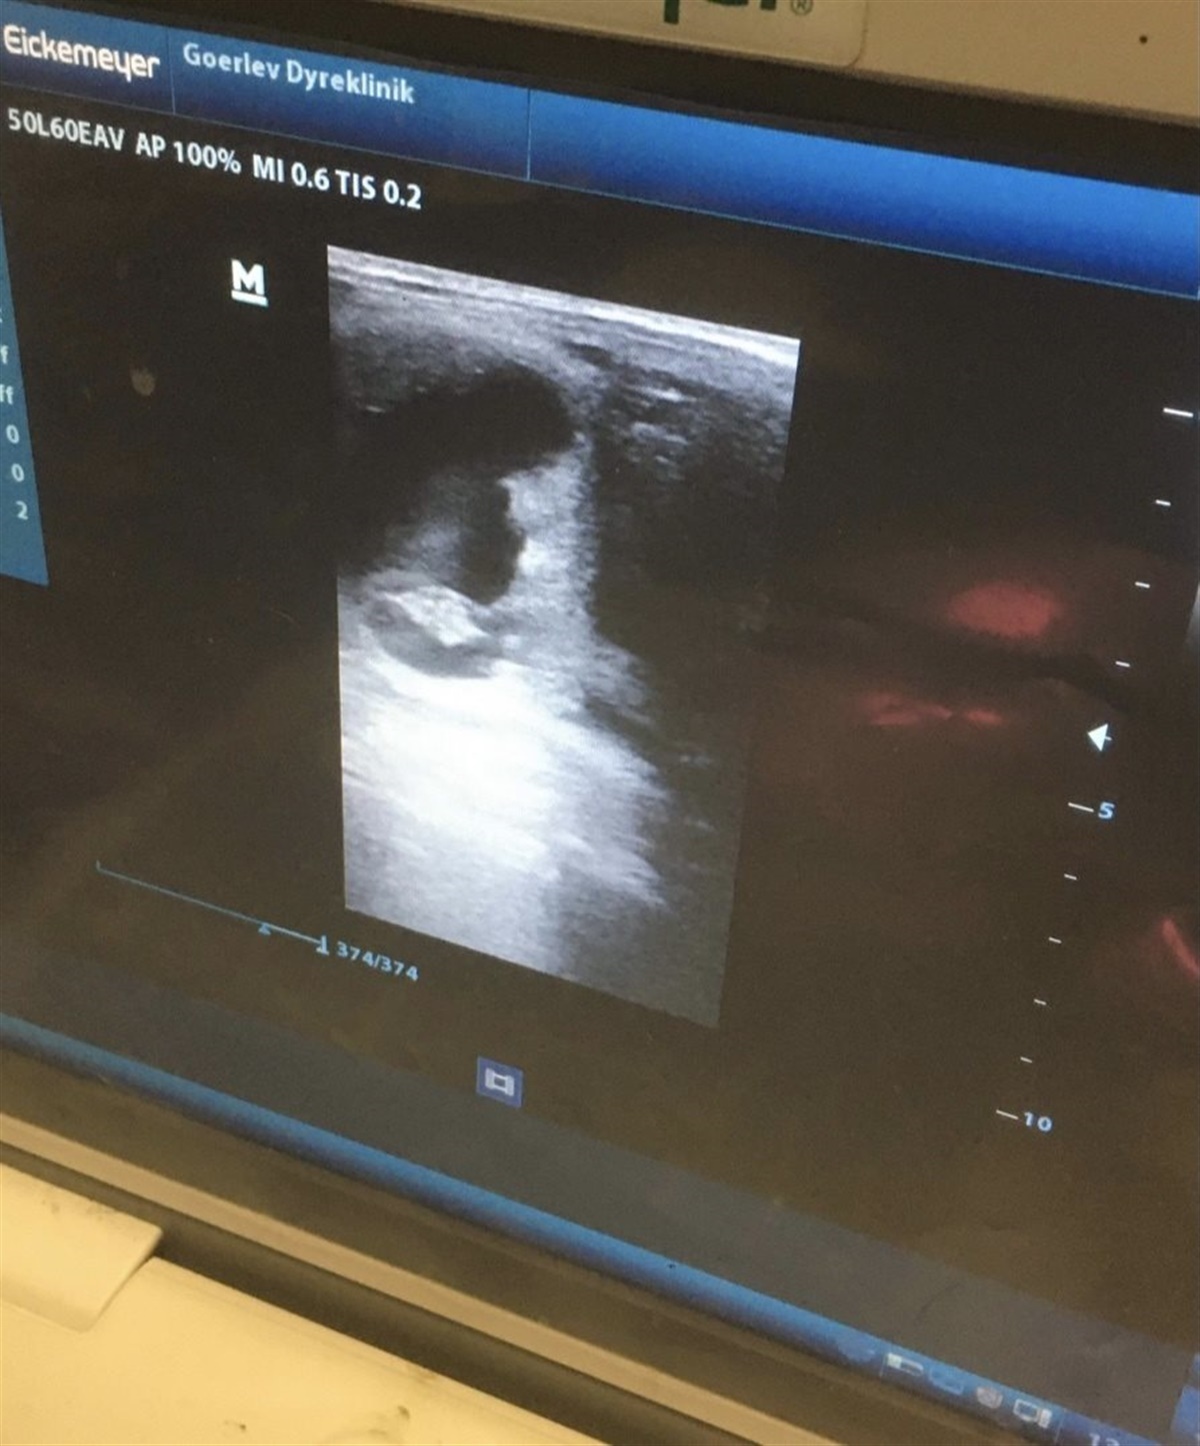

Meningen var dog at tiden som “mini avler” skulle være kort, men som nævnt tidligere ved man aldrig hvad morgendagen bringer. Jeg kom nemlig i den ærgerlige situation at Panda blev skadet. Vi blev derfor enige om at dette var chancen for at lave et formidabelt føl. Vi har derfor valgt at sætte Panda i fol med Hesselhøj Donkey Boy. D. 28. maj blev Panda scannet drægtig i 2. forsøg. Jeg lykkelig over, at jeg næste år kan tage imod et føl efter min helt fantastiske hoppe.